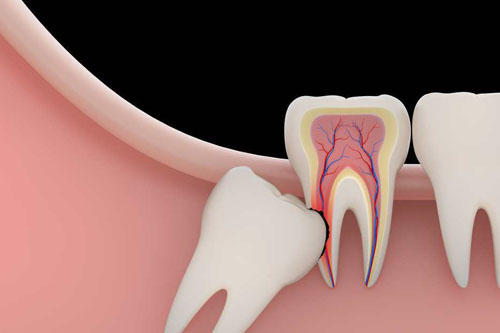

¿Qué hacer en caso de un diente roto?

En caso de un diente roto, es importante mantener la calma y acudir a un dentista lo antes posible. Si hay fragmentos del diente, guárdalos y evita masticar con la zona afectada.